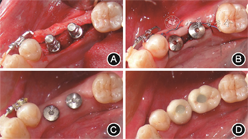

(5)种植治疗:2019年9至11月先后进行35、36、14、17、44种植体植入(图11)。其中,35植入4.1 mm×10.0 mm(S,RN,SLActive,Straumann,瑞士)植体,36、17植入4.8 mm×10.0 mm(S,RN,SLActive,Straumann,瑞士)植体,14、44植入 3.3 mm×10.0 mm(BL,NC,SLActive,Straumann,瑞士)植体。